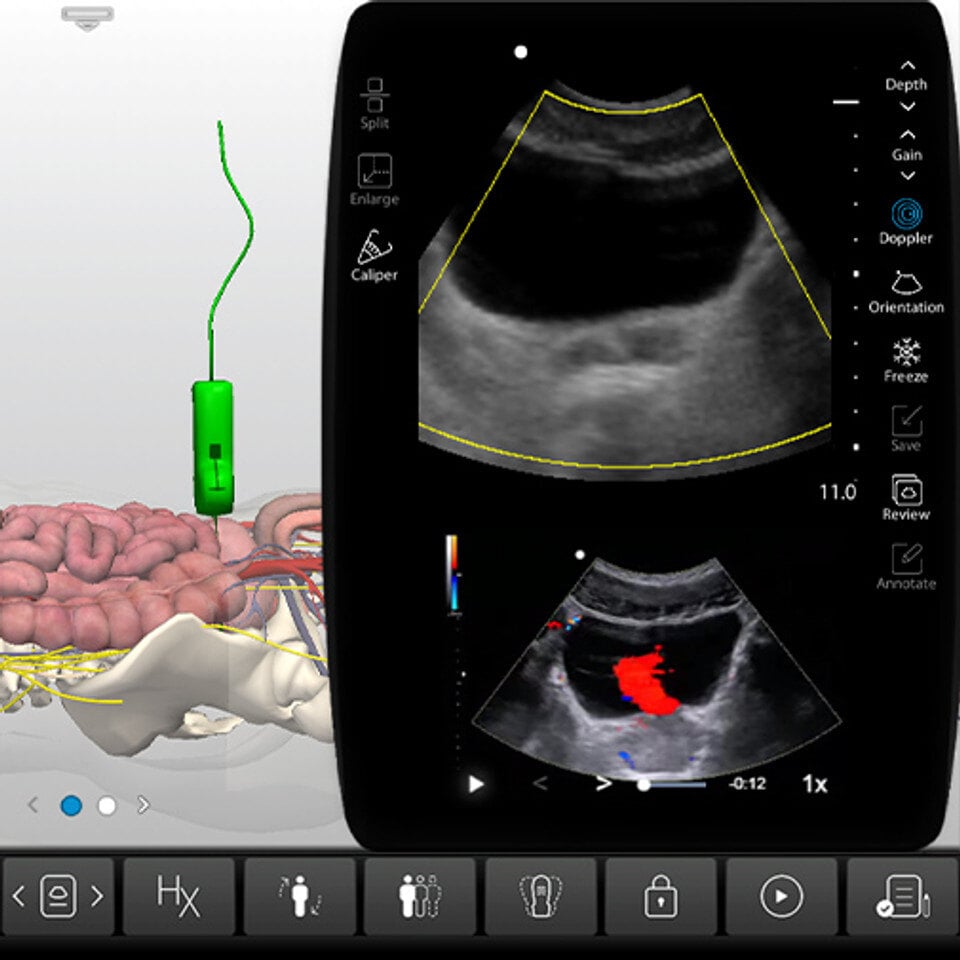

Hands-On Scanning in the SonoSimulator®

After completing the courses, practice with real pathologic cases in our SonoSimulator®. Simulate the experience of scanning real pathologic cases on your computer.

Develop ultrasound image acquisition and interpretation skills with our patented SonoSimulator®. Our innovative platform provides hands-on practice with on-screen probe guide and virtual tutor on-demand overcoming the primary barriers to learning how to scan and read ultrasound.

An on-screen probe guide provides precise image acquisition guidance & virtual layers help develop visuospatial skills

Ultrasound experts narrate key findings & provide imaging tips / real-time feedback

- Doppler & Imaging Modes: Color-Flow Doppler

- Special Case Features: Additional Abdominal/Pelvic CT Imaging, Anatomic Layer Removal